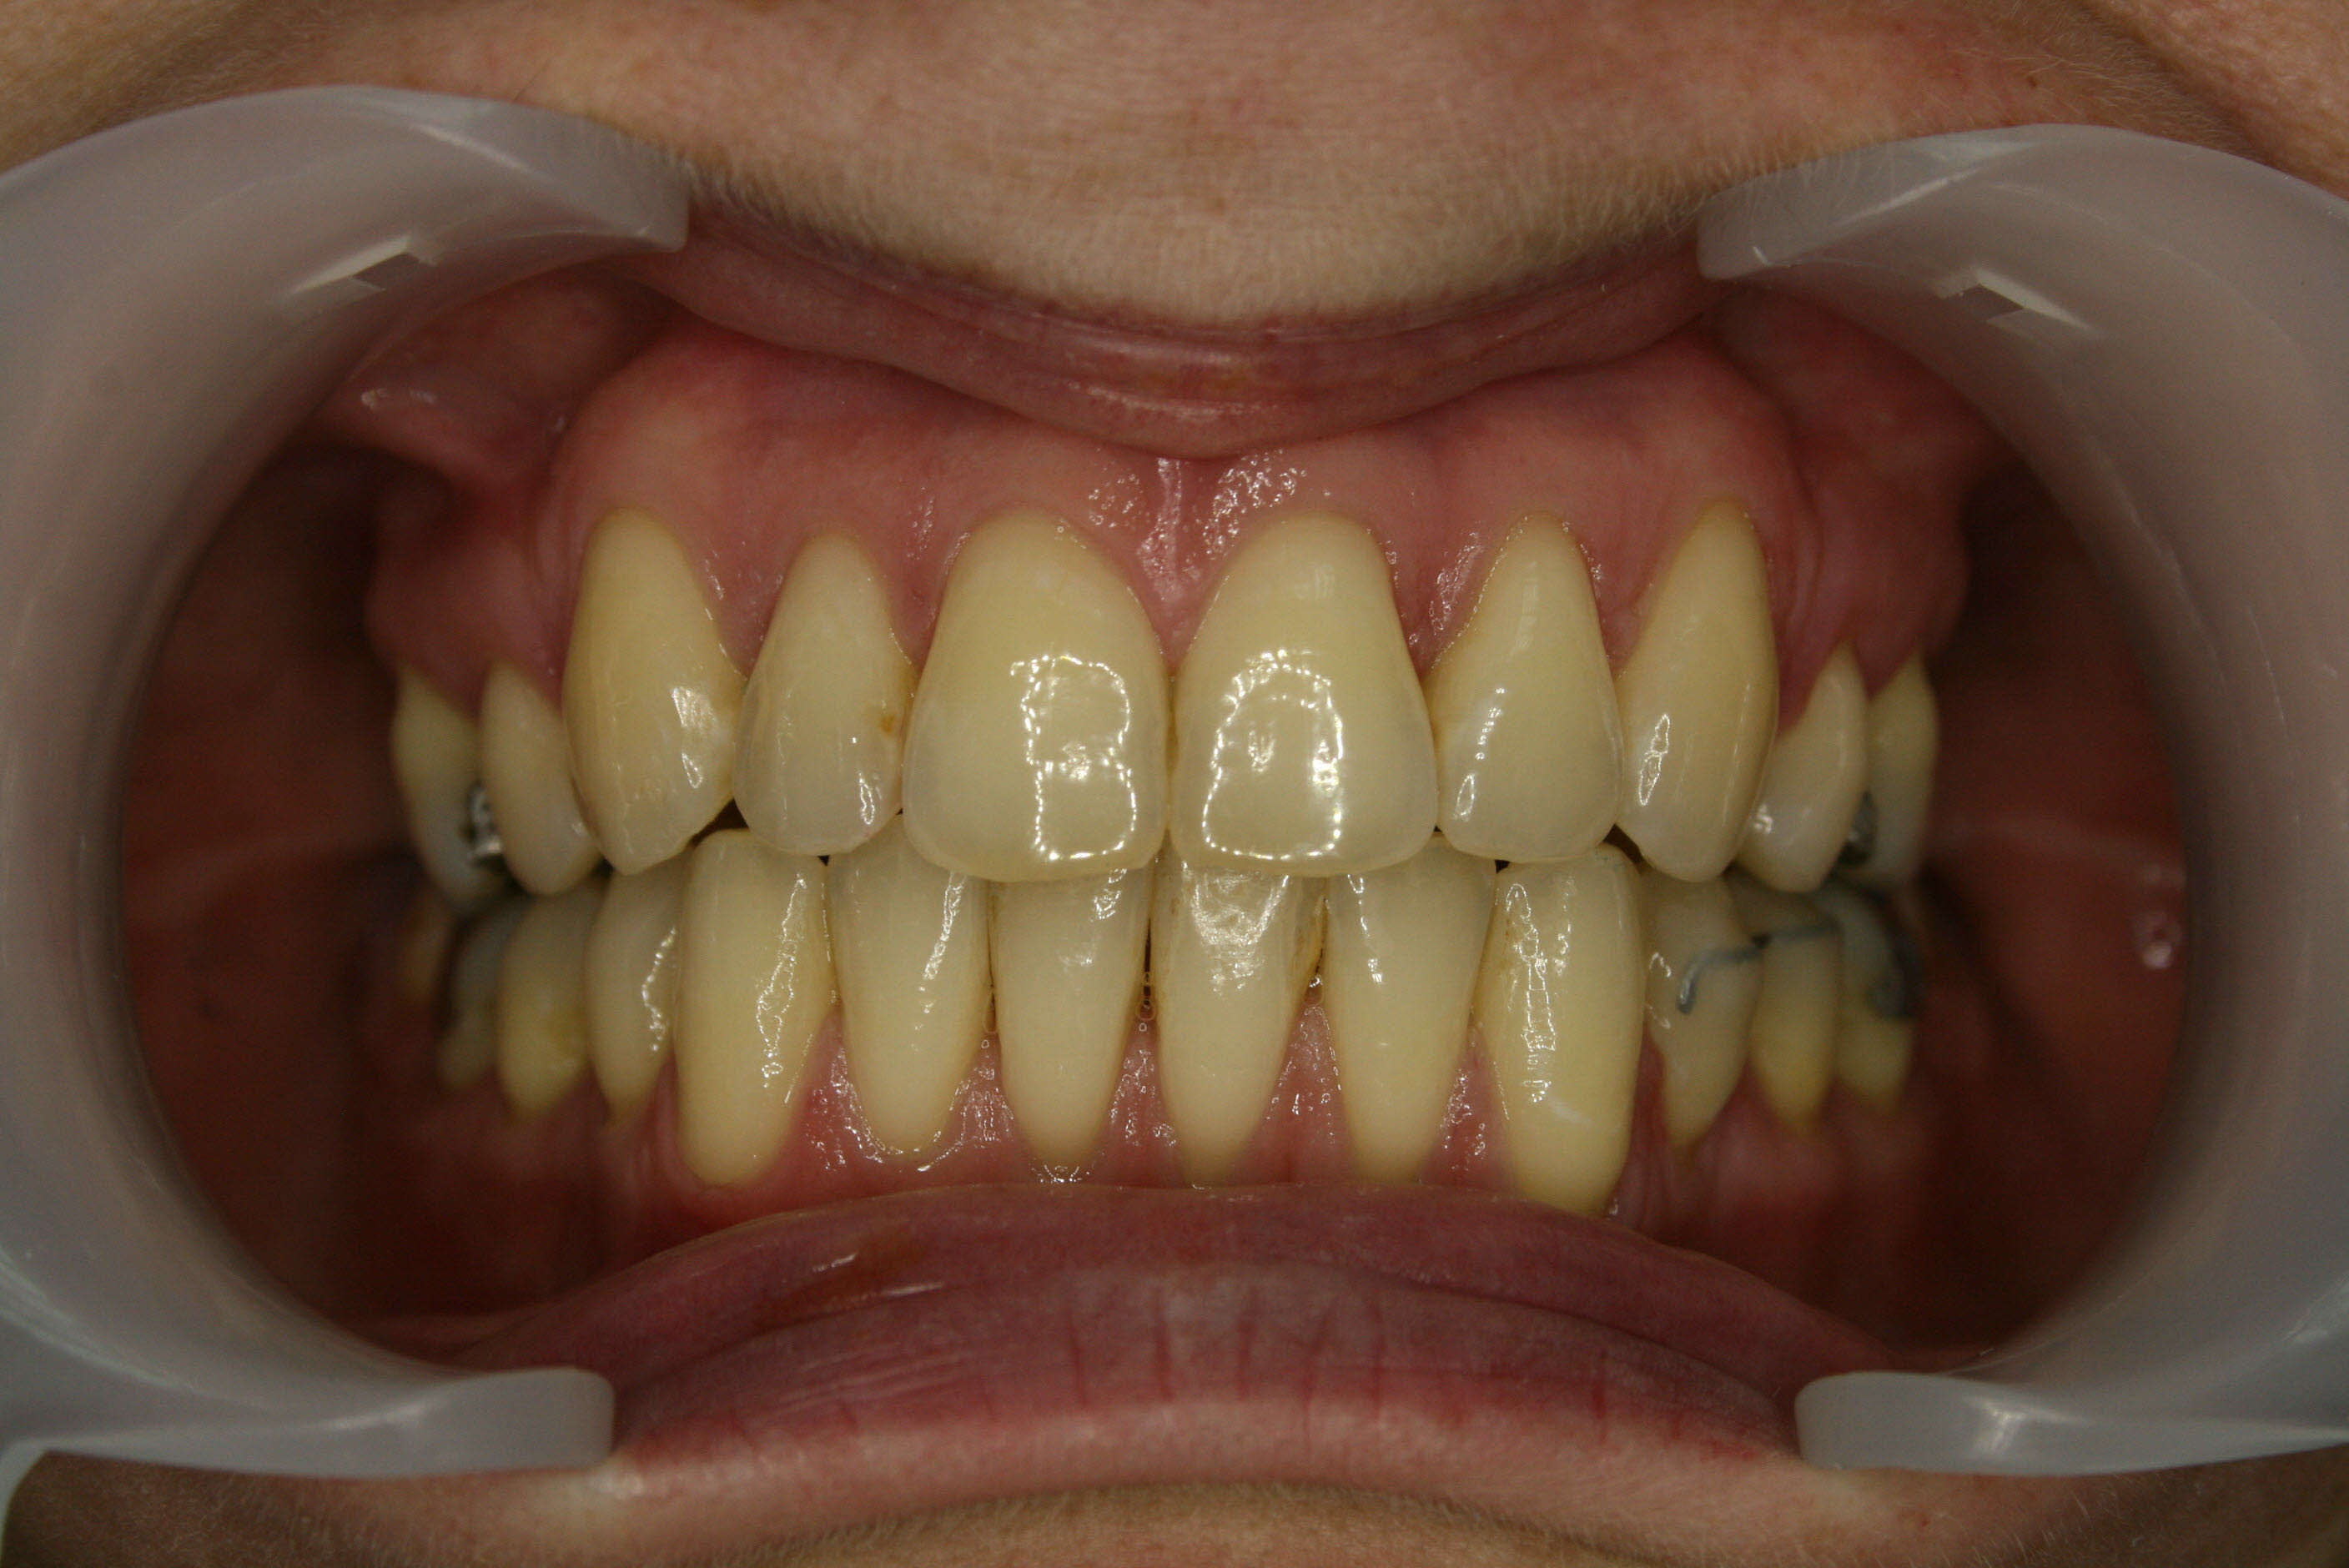

Nach der Behandlung

Die Normalisierung der Achsenstellung der oberen Schneidezähne erlaubte einen entspannten Lippenschluß und ein ansprechenderes Erscheinungsbild der oberen Zahnreihe beim Lächeln.